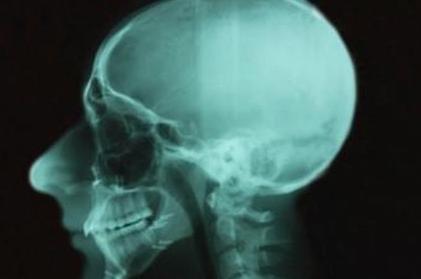

ВНЧС — это сокращение от височно-нижнечелюстных суставов. Эти суставы являются шарнирами, которые соединяют нижнюю челюсть с черепом. Это очень подвижный сустав, способный легко двигаться вверх и вниз, а также вперед и назад. Один из самых важных суставов в вашем теле, ваш височно-нижнечелюстной сустав позволяет вам есть, пить и говорить.